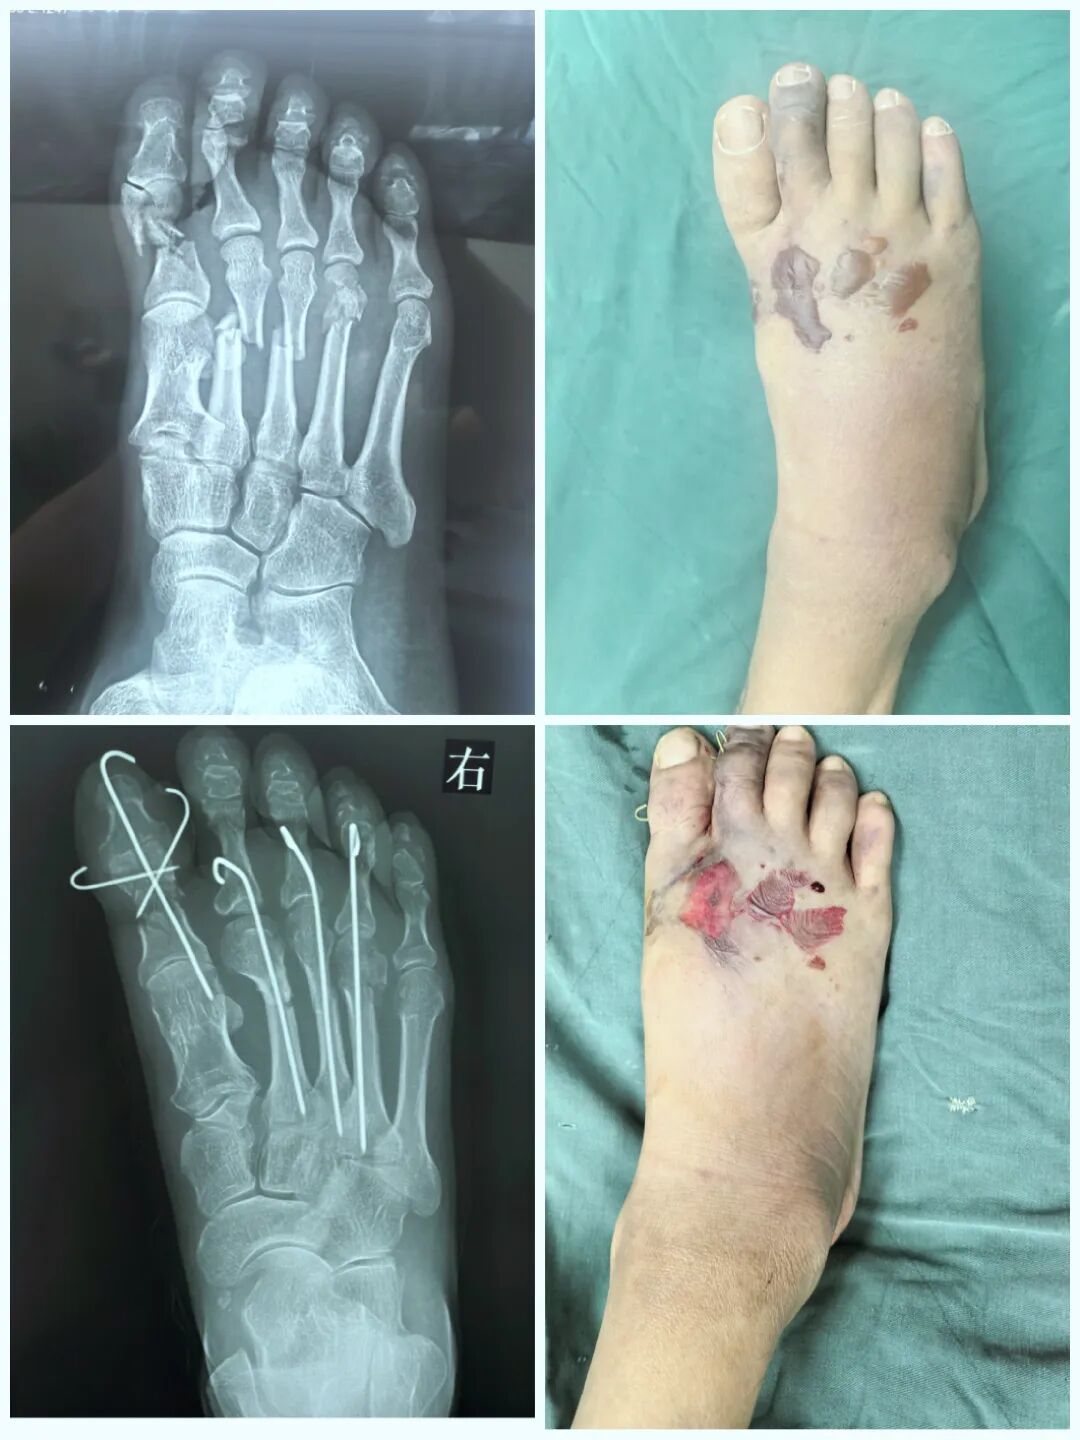

跖骨骨折常伴严重软组织损伤,治疗需兼顾骨性稳定与软组织保护。逆行髓内克氏针技术以微创方式实现有效内固定,尤其适用于多发骨折、开放损伤或软组织条件差的患者。其操作简便、血运破坏少,在损伤控制中展现独特优势。本文通过四例典型病例,探讨该技术在闭合性、开放性及严重毁损伤中的临床应用价值。

闭合性2-5跖骨骨折

逆行髓内针